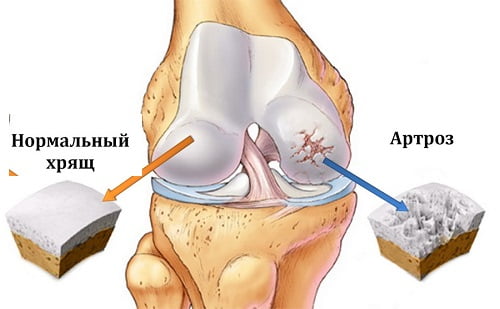

Артроз коленного сустава характеризуется тем, что происходит процесс разрушения хряща сустава. Из-за нарушения обмена веществ, хрящевая ткань не получает необходимых питательных веществ и жидкости, вследствие чего происходит ее дегенерация.

Деформирующий артроз коленных суставов развивается постепенно, по мере нарушения функционирования внутрисуставных хрящей, выстилающих поверхность мыщелков бедренной кости и суставных поверхностей надколенника и большой берцовой кости. Это состояние является следствием недостаточности кровообращения в области коленного сустава.

В результате необеспеченность хряща необходимыми питательными веществами приводит к его ссыханию, расслойке и разрушению. Костная ткань при истончении или полном исчезновении гиалинового хряща уплотняется, при этом образуя компенсаторные разрастания по периферии.